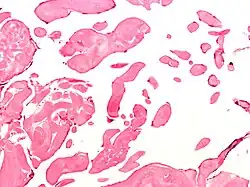

Low magnification micrograph of an excised aortic valve papillary fibroelastoma showing the characteristic avascular branching papillae, H&E stain | |

Papillary fibroelastoma are typically found and accurately diagnosed by imaging. The diagnosis is confirmed by pathology. Histologically, papillary fibroelastomas have branching avascular papillae, composed of collagen, that are covered by endothelium.